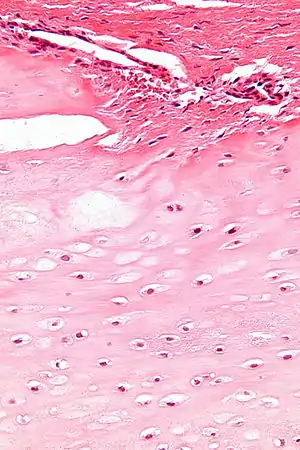

| Enchondromas are present in Maffucci syndrome | |

Maffucci syndrome is a very rare disorder in which multiple benign tumors of cartilage develop within the bones (such tumors are known as enchondromas).[1] The tumors most commonly appear in the bones of the hands, feet, and limbs, causing bone deformities and short limbs.[1]

The enchondromas affect the extremities and their distribution is asymmetrical. The most common sites of enchondromas are the metacarpal bones and phalanges of the hands. The feet are less commonly afflicted. Disfigurations of the extremities are a result. Pathological fractures can arise in affected metaphyses and diaphyses of the long bones and are common (26%). The risk for sarcomatous degeneration of enchondromas, hemangiomas, or lymphangiomas is 15–30% in the setting of Maffucci syndrome. Maffucci syndrome is associated with a higher risk of CNS, pancreatic, and ovarian malignancies. Multiple enchondromas may present in three disorders: Ollier disease, Maffucci syndrome, and metachondromatosis. It is important to make the distinction between these diseases, particularly Ollier disease and Maffucci syndrome. Ollier disease is more common than Maffucci syndrome, and presents with multiple enchondromas often in a unilateral distribution. However, hemangiomas and lymphangiomas are not seen in Ollier disease. Metachondromatosis demonstrates autosomal-dominant transmission and presents with both multiple osteochondromas and enchondromas.